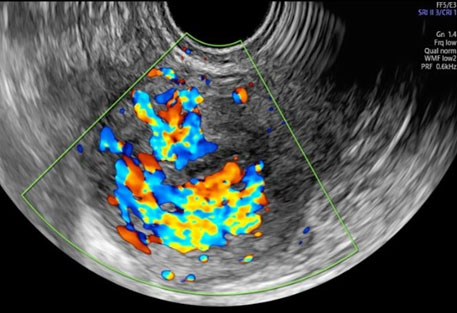

A 34-year-old nulliparous woman underwent medical treatment with misoprostol for an anembryonic pregnancy at nine weeks of amenorrhea. After two weeks a follow-up transvaginal ultrasound (TVUS) showed no retained products of conception (RPOC) with an endometrial thickness of 2.2 mm. It was found an interrupted endometrial-myometrial border in correspondence of a round myometrial lesion of 43×29×31 mm located in the posterior uterine wall (Figure 1). This myometrial lesion was described according to Morphological Uterus Sonographic Assessment (MUSA) terminology for gray scale and Doppler evaluation. Sonographic features showed in Figure 1 at gray scale were: undefined margin, non-uniform echogenicity with multiple irregular internal hypoechogenic spaces. Doppler images showed intralesional multiple vessels and a color score of 4 (Figure 2). The highest peak systolic velocity (PSV) was 31 cm/sec. Ultrasound was performed by an expert sonographer (S.S) with GE Voluson E8 equipment (GE Healthcare, Zipf, Austria) with vaginal probe frequencies of 4–7 MHz. Pulse repetition frequencies for color Doppler used were 600–900 MHz. The highest PSV was recorded with 1 mm window in multiple measurements. According to Italian national protocol on misoprostol use for miscarriage all patients undergo to a TVUS after two weeks to check treatment outcome and presence of RPOC. The β-human chorionic gonadotropin (hCG) value was 13 mIU/mL at time of first ultrasound examination.

Figure 2: Color Doppler image demonstrating turbulent flow and abundant vascularization within hypoechogenic spaces (“mosaic fire ball appearance”).